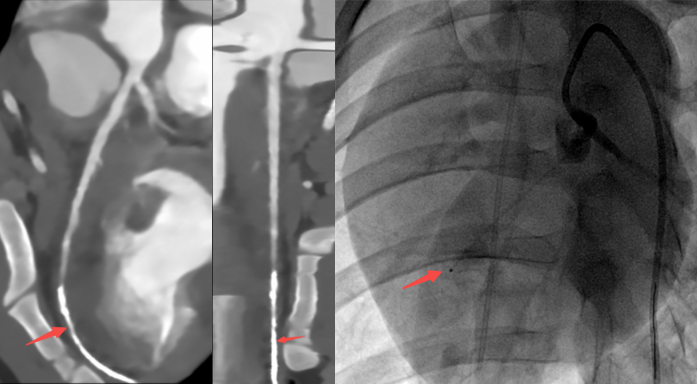

上述二图,皆出自同一人、同一种、同一次检查图像,乃冠脉CTA图像

基于这些突破,uCT SiriuX给我们带来了很多惊喜,文中开头所展示的冠脉CTA生成类DSA、类MR图像功能只是冰山一角,让我们进一步了解该设备在医院的实际临床应用及图像质量。

传统CT通常只能提供单时相静态结构成像,但uCT SiriuX打破了局限,可提供全心动周期多个时相的清晰结构成像信息,动态展示心脏结构运动变化,达到了类DSA、类MR的效果。

全新双宽体CT系统uCT SiriuX凭借全脏器覆盖能力,实现 “全域” 心脏多维成像评估,即注射一次对比剂可同时获取冠脉CTA、心肌灌注、心脏能谱成像和心肌延迟强化等多维图像信息,初步验证结果与DSA、MR心肌灌注、MR延迟强化等金标准影像手段有较高一致性。这对于需要同时进行解剖与功能性评估的患者来说,方便省事了许多。

冠脉CTA  VS DSA

CT心肌灌注 VS MR心肌灌注

CT心肌延迟显像 VS MR ECV(心肌细胞外容积)